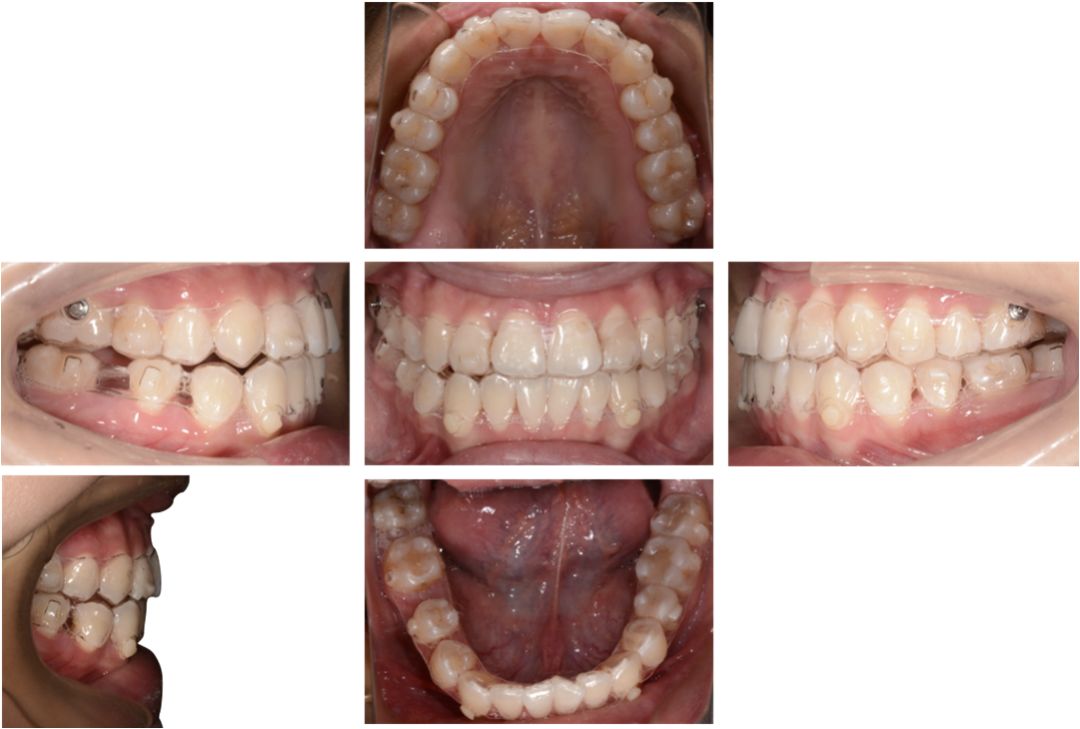

口腔检查:

上下牙弓呈方圆形;双侧尖牙、磨牙III类关系;21牙与31牙呈切合;前牙呈现约1 mm的局部开合;下颌中线较上颌中线左偏1 mm。

上颌拥挤度:1.5 mm,下颌拥挤度:1.5 mm。Bolton指数:全牙比为86.70%,前牙比为75.5%。患者上下颌牙列均存在前牙段轻度的拥挤,前牙和全牙的bolton指数均偏小,提示上颌牙齿牙冠宽度偏大。